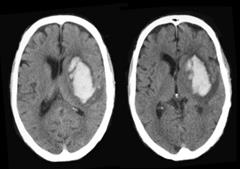

Складають 10-12% всіх випадків інсульту. Ключовою ознакою є швидке прогресування неврологічного дефіциту; великі за розміром крововиливи часто на початку дають розлади свідомості (коми). Характер і важкість неврологічного дефіциту залежить від локалізації та розмірів гематоми. Найбільший ризик крововиливів мають люди з неконтрольованою гіпертензією (утворення мікро аневризм Шарко-Башара). Інші причини: амілоїдна ангіопатія (у людей, старших 70), пухлини, коагулопатії та вживання антикоагулянтів, аневризми та судинні мальформації, зловживання алкоголем та наркотичними речовинами, травма та крововилив у зону мозкової ішемії. Діагноз встановлюється на КТ та МРТ. Хірургічне лікування, як терапія, що врятовує життя, показана при великих лобарних супратенторііальних та мозочкових гематомах, які звичайно порушують свідомість та спроможні викликати дислокацію мозку.

Порушена свідомість, великий розмір гематоми, зміщення серединних структур на КТ та прорив крові у шлуночки – негативні фактори для прогнозу. В частині випадків, хірургічне видалення гематом (особливо мозочкових та лобарних) є життєво необхідним (хоча і не впливає на неврологічний дефіцит). Відмінним у веденні хворих з геморагічним інсультом є жорсткий контроль за зниженням артеріального тиску (до 140/90 мм рт ст.).